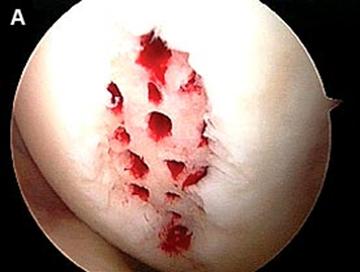

Fig.22. Debridarea (a, b, c).

a. b.

Fig.25.a. Debridarea. Fig.25.b. Microfracturare.

Dupa indepartarea cu succes a stratului de cartilaj calcifiat, o andrea este folosita pentru a face mai multe gauri mici (mirofracturi) in osul expus al defectului condral aflate la distanta de 1-2 mm. Trebuie lasata o punte de oase potrivita intre gauri. Tehnica de microfracturi are numeroase avantaje fata de foraj. Mai intai de toate, creaza o leziune termala mai mica. Mai mult, cu microfracturi, chirurgul este capabil sa intre in zonele dificile ale suprafetei articulare cu un control mai bun asupra adancimii de patrundere. La finalizarea microfracturii, o suprafata aspra este generata pentru a aderenta cheagului de sange care contine celule mezenchimale nediferentiate de la osul subcondral. Trebuie avut grija ca cele mai marginase parti ale leziuni sa fie patrunse de andrea pentru a ajuta la vindecarea tesutului reparator la imprejmuirea suprafetei articulare. Odata ce microfractura este finalizata, pompa artroscopica este oprita pentru a se asigura ca sangerarea maduvei curge din gaurile mici umpland defectul.[54]